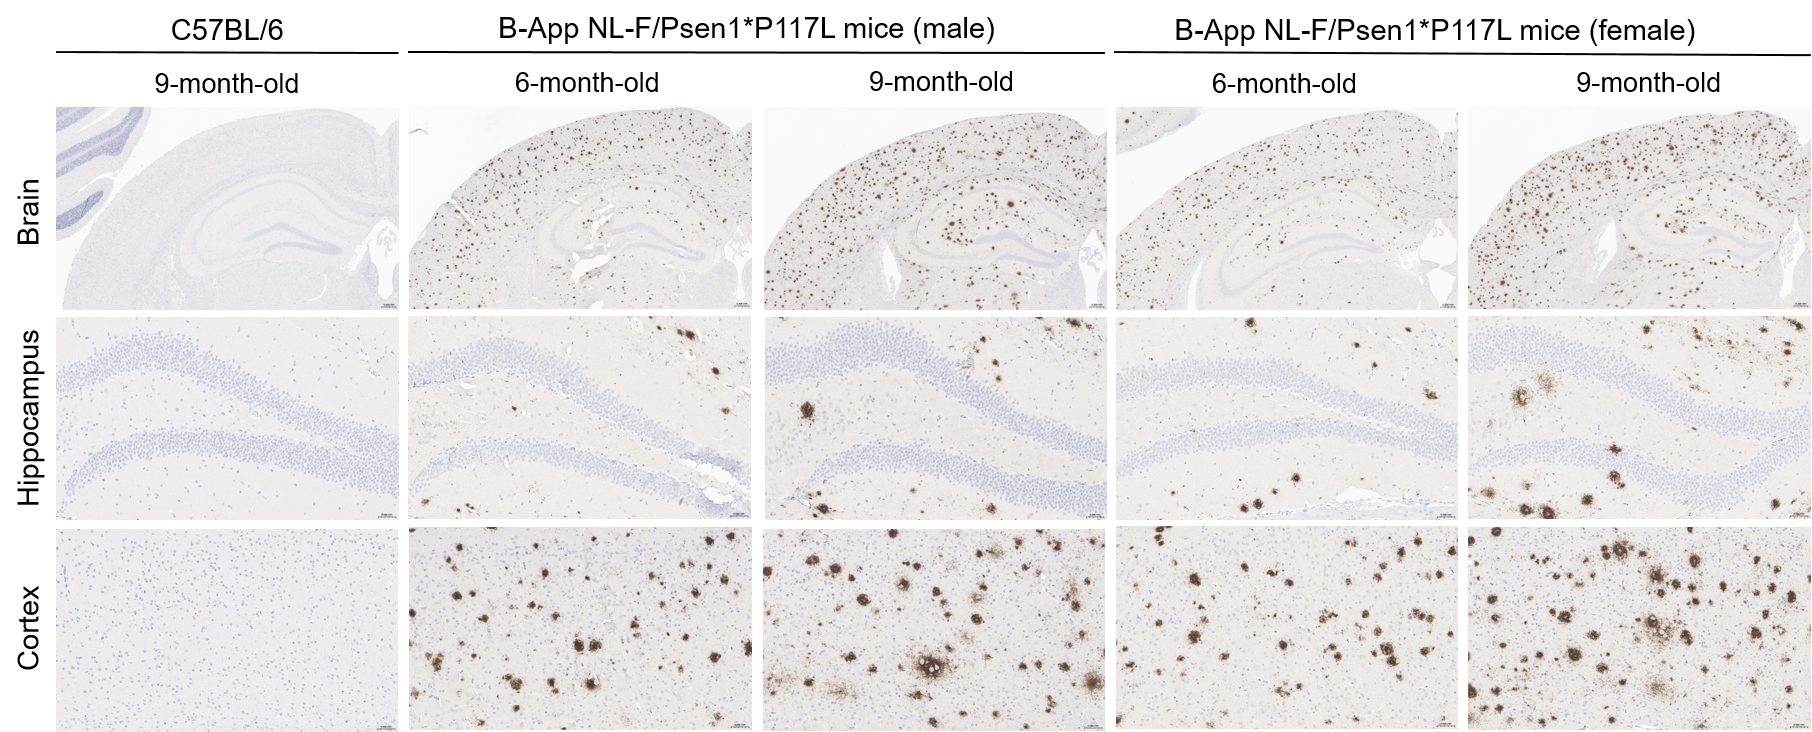

Immunohistochemistry Analysis-Aβ Deposition

Histopathological analysis of Aβ in homozygous B-App NL-F/Psen1*P117L mice. Brain was collected from wild-type C57BL/6 mice (9-month-old) and homozygous B-App NL-F/Psen1*P117L mice (6-month-old and 9-month-old) and processed into paraffin sections. The Aβ plaque was detected in the cortex and hippocampus of 6-month-old and 9-month-old homozygous B-App NL-F/Psen1*P117L mice with anti-human β-Amyloid antibody (CST, #8243S). The burden of Aβ immunoreactivity was increased in an age-dependent manner. Scale bar: 50 μm.